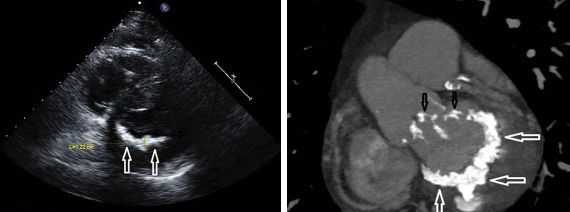

Другой важный инструментальный метод диагностики — эхокардиография (Эхо-КГ) . Эхо-КГ — это безболезненное ультразвуковое исследование, которое позволяет исследовать работу сердца в реальном времени. Эхокардиография покажет уменьшение эластичности клапана, его повреждение, размер отверстия митрального клапана и расстояние между его створками. Также при исследовании можно увидеть разрыв папиллярной мышцы и провисание клапанных створок в полость левого предсердия [4] [8] [9] .

- Эхокардиография (УЗИ сердца). Здесь врач может обнаружить такие признаки болезни, как провисание створок митрального клапана (задней или сразу обеих) в полость левого предсердия в середине систолы, в позднюю систолу или во всю систолу. Эхокардиография - это одно из самых важных обследований в диагностике ПМК у пациента.

Эхокардиография (УЗИ сердца) - это главный метод исследования для диагностики ПМК. С его помощью оценивается тяжесть пролапса: степень пролабирования створок и регургитации. Под пролабированием подразумевается то, насколько створки клапана прогибаются в полость левого предсердия.